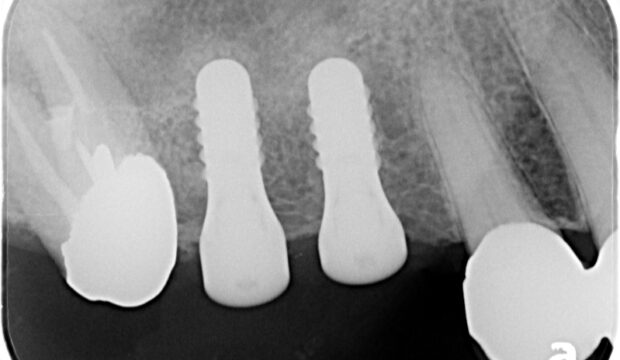

インプラント症例その8

インプラント症例その7